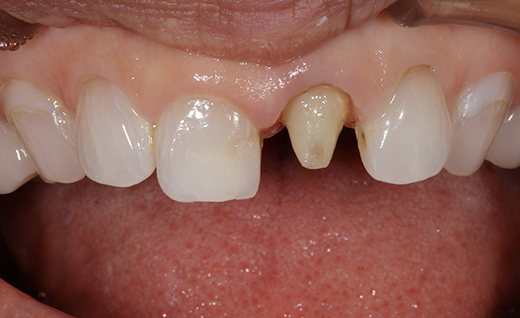

施術中

施術中です。このように新しいオールセラミックを被せるための土台を形成していきます。